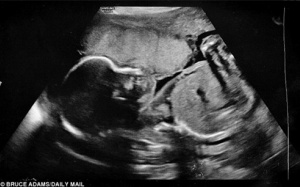

Bất ngờ bị vỡ ối non ở tuần 22 thai kỳ, bà mẹ này đã làm một việc không ai ngờ và cuối cùng đã giữ được con yêu.